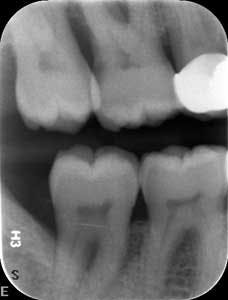

Dental examination revealed gingival swelling and bleeding on probing. Periodontal probing showed moderate-to-deep pocket depths in all posterior teeth (figures 1–3). Generalized bone loss was observed on radiographs (figures 4–6). Tooth vitality and percussion tests were negative. Teeth 2, 3, 31, 14, and 15 had Class III mobility. The patient was diagnosed with Type IV chronic adult periodontitis. Treatment options were discussed, and, after explanation, the patient agreed to the LANAP procedure.

Patient presentation before LANAP treatment (figures 1–6)